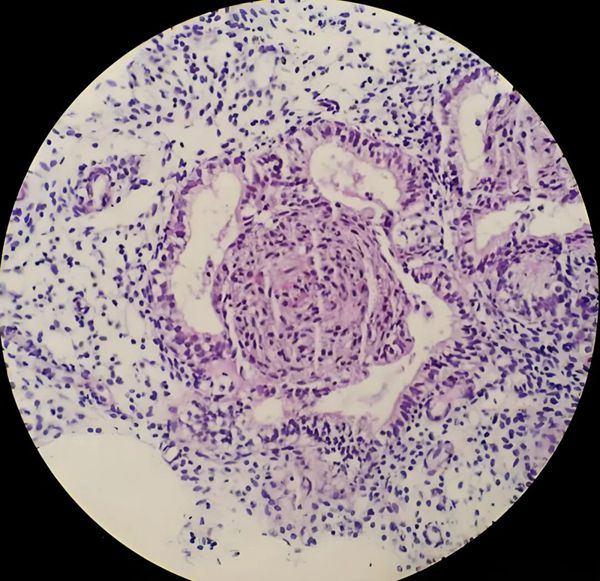

2、内膜免疫细胞紊乱:CD138阳性,提示慢性子宫内膜炎;

慢性子宫内膜炎:很隐蔽!会导致内膜免疫紊乱,着床失败,需抗生素+免疫调理;